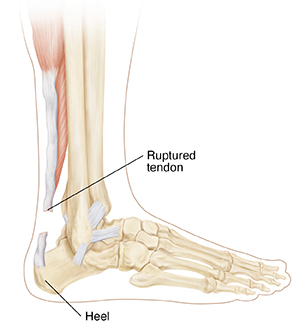

Achilles Tendon Rupture

Your Achilles tendon is a large band of tissue in the back of your ankle. It connects your calf muscles to your heel bone. The tendon helps you point your foot down, rise on your toes, and push off when you walk. You use it almost each time you move your leg. But repeated stress can make the tendon more prone to injury. It may become inflamed and develop small tears (tendonitis). A complete tear through the tendon is called an Achilles tendon rupture.